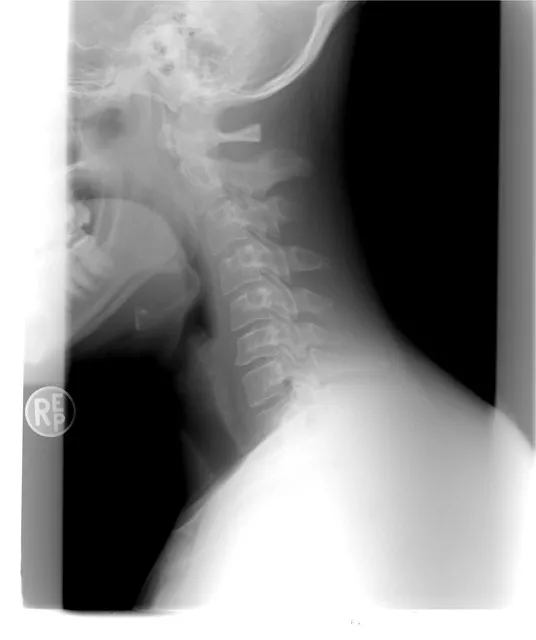

如何进行脊髓型颈椎病的诊断?

脊髓型颈椎病的诊断依赖于临床信息、辅助检查结果及医生经验。首先,医生会询问患者的症状及病史,注意到如走路不稳、四肢无力等神经症状。

接着,基础的体格检查如神经系统查体是必不可少的,通过检查肌力、肌张力、反射等方面,可以初步判断病情的严重程度和具体部位。

辅助检查方面,CT和MRI是诊断脊髓型颈椎病的金标准。CT可以清晰显示骨性结构的变化,如骨刺和椎体变形;而MRI则更侧重于软组织的显示,如椎间盘突出、脊髓受压情况等。

医生会结合临床表现、检查结果及自己丰富的临床经验综合判断,最终确诊。这一过程中,应用最新的循证医学证据,有助于提高诊断的准确性。